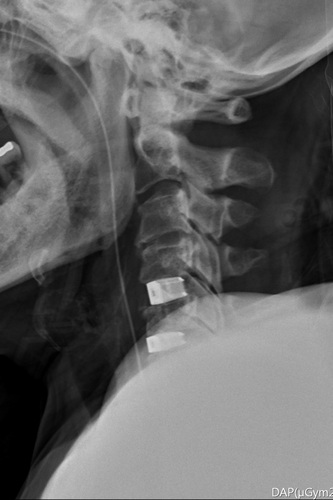

李建輝主任表示,當時在急診看到婦人,除主述四肢癱軟無力,發現她一直在用腹式呼吸,無法自然呼吸,令他警覺有可能是頸椎神經受損,因為控制橫膈的神經就在頸椎附近,透過檢查果然是第四到六節的神經被壓迫,且能清楚看到她的骨刺壓迫已造成脊髓損傷,有癱瘓風險,須儘快手術清除和重建,提高恢復的可能性,隨即在隔天進行手術,清除突出的椎間盤後放入填充物,並用支架固定頸椎。

圖:李建輝醫師以脊椎內固及融合微創手術,清除突出的椎間盤後放入填充物,並用支架固定頸椎。